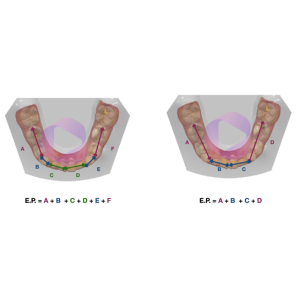

Os pacientes com relação esquelética de Classe III são aqueles em que a mandíbula se encontra para anterior em relação à maxila, ou seja, a maxila é pequena no sentido ântero-posterior em relação à mandíbula.

Hoje é consenso na literatura de que a protração não precisa ser necessariamente precedida pela expansão maxilar, porém o que observamos no dia a dia da clínica, é que a guarde maioria dos pacientes com maloclusão esquelética de Classe III possuem também atresia de maxila.

Isto porque, de maneira geral, quando nos deparamos com uma maxila “pequena” no sentido ântero posterior, é comum que esta também seja estreita, ou seja, a maxila é “pequena” como um todo em relação à mandíbula.

Na imagem acima é possível observa a relação oclusal de um paciente Classe III esquelética onde a maxila também se encontra atrésica em relação à mandíbula.